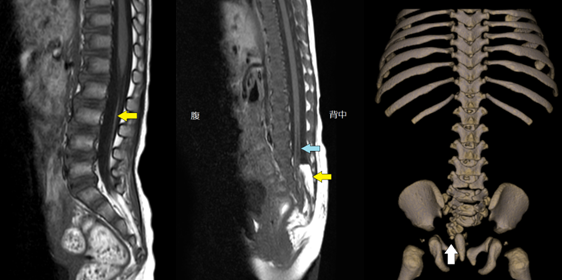

したがって、この状態は通常、別の理由で受けた X 線またはMRI スキャンによって偶然発見されます。

これらには、症状が存在することを確認するための X 線または MRI スキャンが含まれる場合があります。